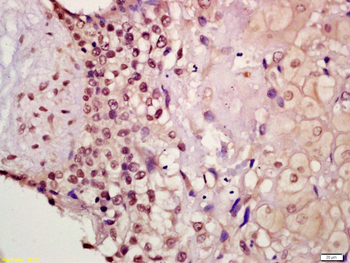

FC, IF, IHC-Fr, IHC-P

应用稀释比例:IHC-P=1:100-500, IHC-F=1:100-500, IF=1:100-500, Flow-Cyt=2ug/Test